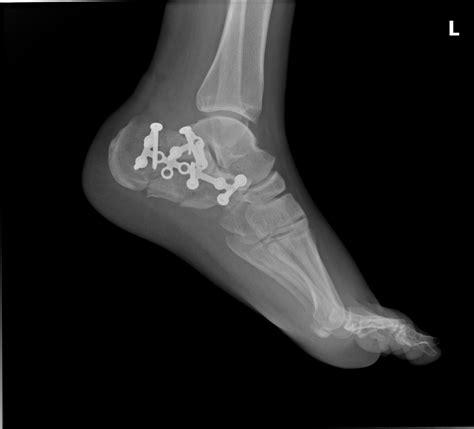

• Surgery: In cases of severe fractures or dislocations, surgery may be necessary to realign the bones and stabilize the joint. Surgical options may include open reduction and internal fixation (ORIF) or arthroscopy.